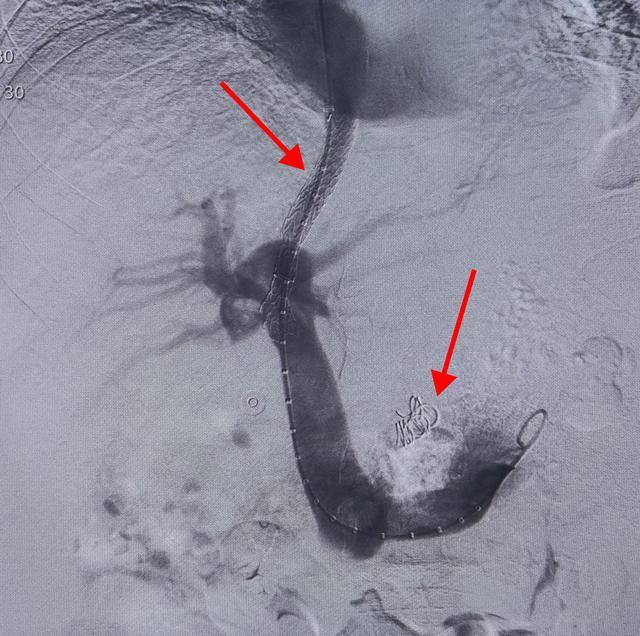

(▲找到消化道大出血的源头——食管胃底静脉曲张(箭头所示))

(▲为高压静脉安装“减压阀”后,出血血管消失)